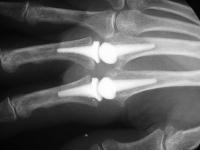

Clinical Example: Pyrolytic carbon metacarpophalangeal joint implant arthoplasty

Pyrolytic carbon implant arthroplasty of the finger joints appears to be an improvement on previous strategies, as it mimics the normal joint mechanics, in movement, lack of wear debris and a close match to the mechanical characteristics of the finger bones.

Pre and postop radiographs.